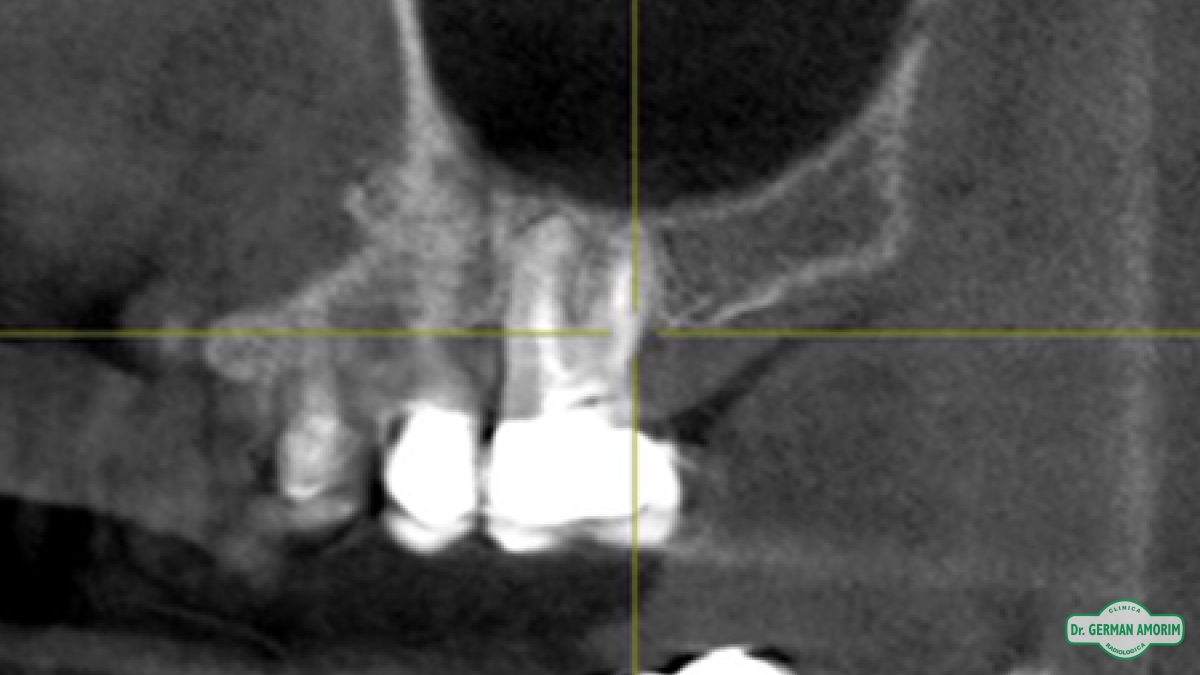

Actualmente y con todos los conocimientos científicos que existen sobre las técnicas implantológicas se recomienda tener siempre una imagen 3D, también en los casos que sea un solo implante. Porque se debe conocer con precisión el espesor de la tabla vestibular para determinar el pronóstico a largo plazo del implante y la única manera de hacerlo es con una tomografía.

En Clínica Amorim contamos con un Tomógrafo de Haz Cónico Orthophos XG de Sirona que mediante la emisión de un haz cónico de rayos genera una serie de imágenes digitales, que son transferidas al computador a partir de las cuales se realiza una reconstrucción en 3D.

El odontólogo utilizando el software específico Galileos puede observar esta imagen en los tres ejes de un espacio tridimensional y trabajar sobre ella para, entre otras cosas, planificar la colocación de los implantes dentales, lesiones ocultas por superposición en las RX convencionales, etc.